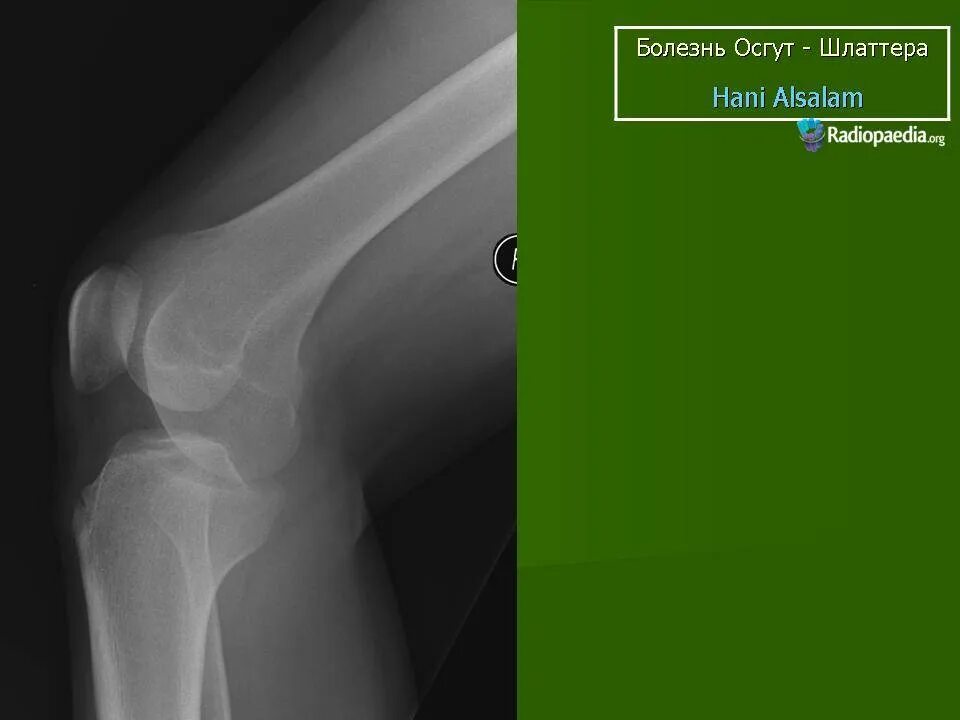

Болезнь осгут шляттера